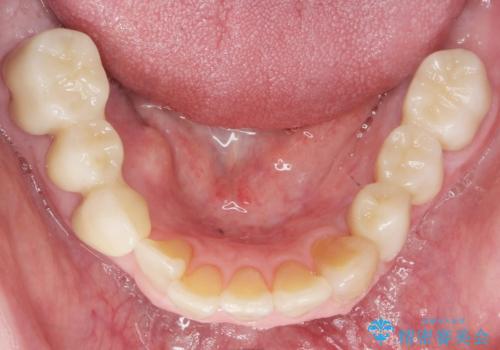

骨を再生させて歯周病を治す 再生療法 50代男性

- 全顎的な重度歯周病の患者様です。

骨吸収の進行している右下臼歯部に、再生療法(骨を増やす手術))を行いました。

再生療法から1年後、リエントリー手術により骨の再生を確認し、骨外科処置(骨を平らにして歯周ポケットの根本的な改善を図る処置)を行いました。

埋伏していた親知らず、保存不可能な右下の一番奥の歯(右下7)、状態の悪い犬歯(右下3)は抜歯しております。

再生療法と骨外科処置により、歯周ポケットは全周2mm以下となりました。

根本的な歯周病の治療を行うことで不安がなくなり、患者様に喜んで頂けました。

奥歯の動揺がなくなりしっかりと咬むことができ、審美的・機能的にもご満足頂けました。